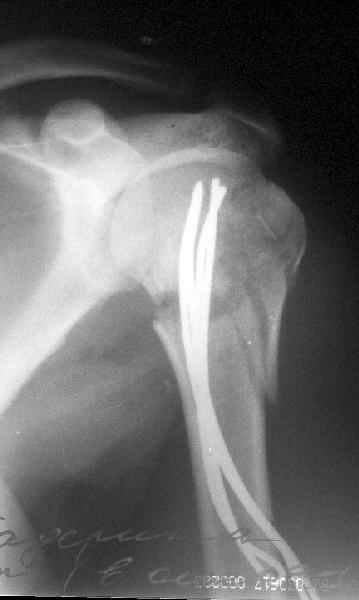

Здесь случай перелома-вывиха плеча, больному 56 лет, после "дважды" закрытой неудачной репозиции, опять же ургентно взяли в операционную, после полного общего обезболивания попытались сделать репозицию, и фиксацию провели спицами.

Да. У нас довольно скромный опыт такого остеосинтеза (по 2 случая - плечо и наружная лодыжка), дошли до использования самого простецкого троакара, через который мы сверлим кость и вводим 6 мм стержни, когда накладываем аппарат. Соответственно, в качестве забойника отлично работает любой стержень от аппарата Илизарова. Еще из наших туземных особенностей - страшная любовь к спицевым дистракторам, поэтому делали в нем. Результат у этой дамы неизвестен, т.к. она из области и уехала рожать сразу после остеосинтеза, сейчас прошло больше 5 месяцев...

Что-то, наверно, сделали мы не совсем оптимально, поскольку у Анатолия Федровича и его соратников как-то красивее "раскрываются" спицы в головке плеча - надеюсь, он прокомментирует и подскажет, что надо подправить.